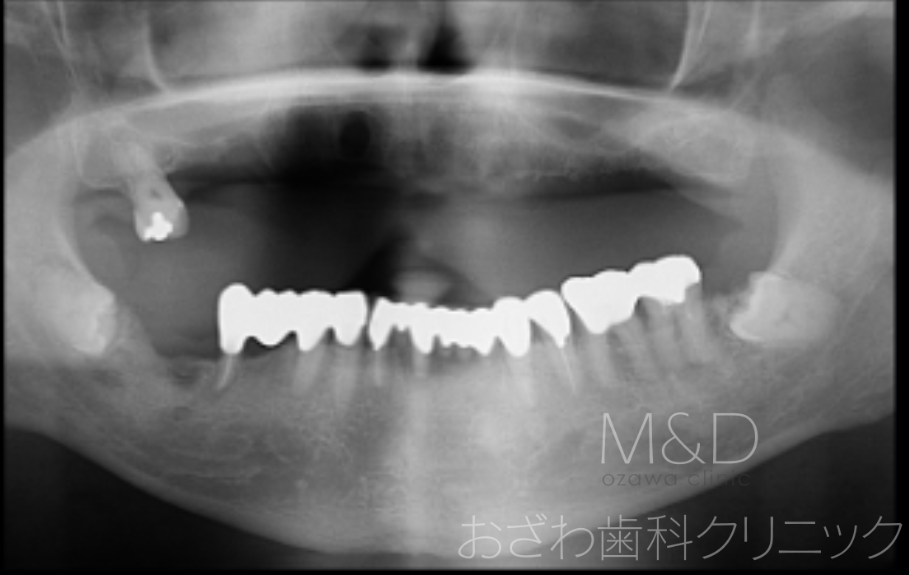

術前

主訴:入れ歯が落ちる、ぐらぐらして痛く、噛めない

上顎残存歯の抜歯、上顎5本(オールオン5)インプラント